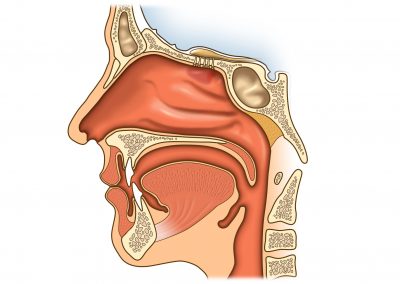

Sinüzitin tanısı; KBB uzmanı bir doktor tarafında ...

Çocuk sinüzitleri, inatçı ve sık sık tekrarlayan bir hastalıktır. ...